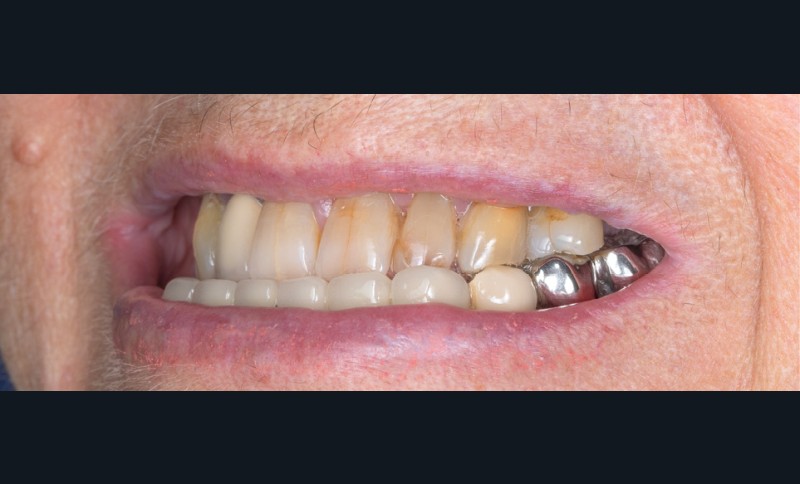

La première étape repose sur la récolte des données cliniques suivantes : – photographies exo- et endo-buccales (fig. 1), utilisées pour l’évaluation esthétique, le diagnostic initial et la communication avec le prothésiste ;